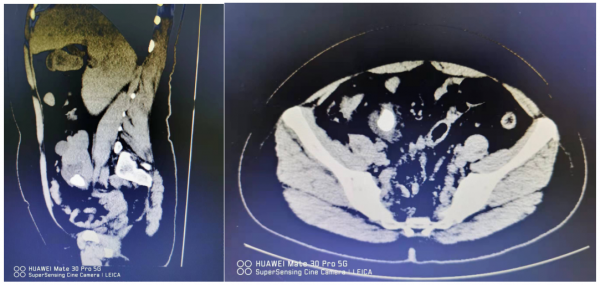

“患者的彩超檢查發現她的右腎出現在盆腔裡,腎門朝向外前方,而正常人的腎臟位於後腰部,腹腔後方、脊柱的兩側後方。”任明華教授介紹,劉女士的右腎還有一顆直徑達3cm多的結石橫在腎盂內,這也是劉女士出現持續疼痛的根源。

手術中,任明華教授帶領齊奧主治醫師透過輸尿管鏡取出輸尿管支架管,在輸尿管鏡下置入導絲,在導絲引導下在迂曲的輸尿管內成功地置入輸尿管軟鏡鞘,用輸尿管軟鏡僅用時40分鐘就成功地將3cm的腎結石成功擊碎,使結石變成粉末狀,再次置入輸尿管支架管後,患者安返病房。在積極的術前抗炎治療與術中碎石時間的控制下,她未出現明顯的感染,術後1天就能順利排氣,下地活動,複查X線不僅能看見結石被完全擊碎,而且可以看到異位腎及周圍臟器保護良好,沒有出血及滲出。幾天後,劉女士順利地出院了。